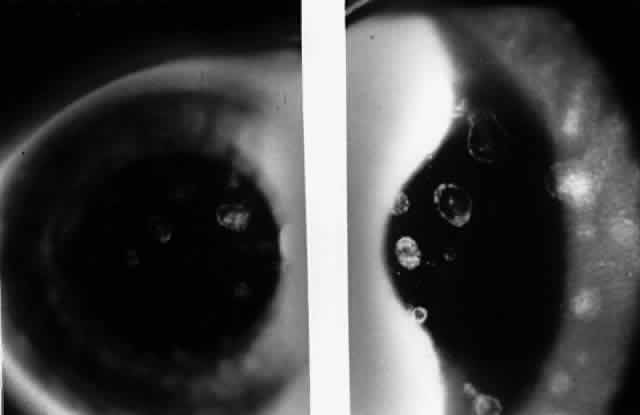

In 1986, Matoba and associates reported 7 patients with purported EBV stromal keratitis, but only 3 of the patients had clinical symptoms of IM or evidence of recent seroconversion.69 In one of the patients, heterophil antibody-positive IM preceded by 1 week the onset of chronic multifocal keratitis. When the authors first examined the patient in referral 9 months later, they found multiple, discrete, anterior stromal opacities in the patient's left eye. In another patient, bilateral, patchy, deep peripheral infiltrative keratitis and a fourfold decrease in antibody against EBV viral capsid antigen were documented at the time of referral 5 months after an “infectious mononucleosis-like illness” associated with bilateral red eyes and photophobia. In another patient, the authors state that IM preceded subepithelial infiltrative keratitis in the left eye by 1 month. When examined 8 months after onset of the keratitis, the patient's left cornea showed features of multifocal anterior stromal and deep peripheral stromal keratitis. Although the other 4 patients in this series did not show evidence of recent EBV seroconversion, their keratitis appeared similar to that of the patients with documented IM. On clinical grounds alone, Matoba and associates postulated that the development of EBV keratitis did not depend on recent EBV infection, but could occur in the chronic carrier state. To summarize the authors' findings in the combined group of 7 patients, the interstitial keratitis appeared in 4 patients as unilateral, multifocal, discrete, sharply demarcated, anterior stromal opacities, 0.1 to 2 mm in diameter, with either a blotchy pleomorphic (Fig. 2) or granular ringlike appearance (Fig. 3), in two patients as bilateral, multifocal, full-thickness or deep stromal peripheral infiltrates reminescent of luetic keratitis (Fig. 4), and in 1 patient with features of both. No patient tested had showed serologic evidence of acute systemic HSV or adenovirus infection. Both patients with keratitis restricted to the peripheral cornea had bilateral disease but lacked serologic evidence for syphilis (nonreactive MHA-TP). Five patients had mild or moderate corneal stromal vascularization. Two patients showed corneal epithelial granularity overlying the stromal opacities.

Fig. 2. Blotchy pleomorphic multifocal anterior stromal corneal infiltrates in a 25-year-old woman. (Matoba AY, Wilhelmus KR, Jones DB: Epstein-Barr viral stromal keratitis. Ophthalmology 93:746, 1986)

Fig. 3. Sharply demarcated ring opacities of the anterior corneal stroma in an 11-year-old boy. (Matoba AY, Wilhelmus KR, Jones DB: Epstein-Barr viral stromal keratitis. Ophthalmology 93:746, 1986)

Fig. 4. Multifocal deep peripheral corneal stromal infiltrates in a 17-year-old man. (Matoba AY, Wilhelmus KR, Jones DB: Epstein-Barr viral stromal keratitis. Ophthalmology 93:746, 1986)